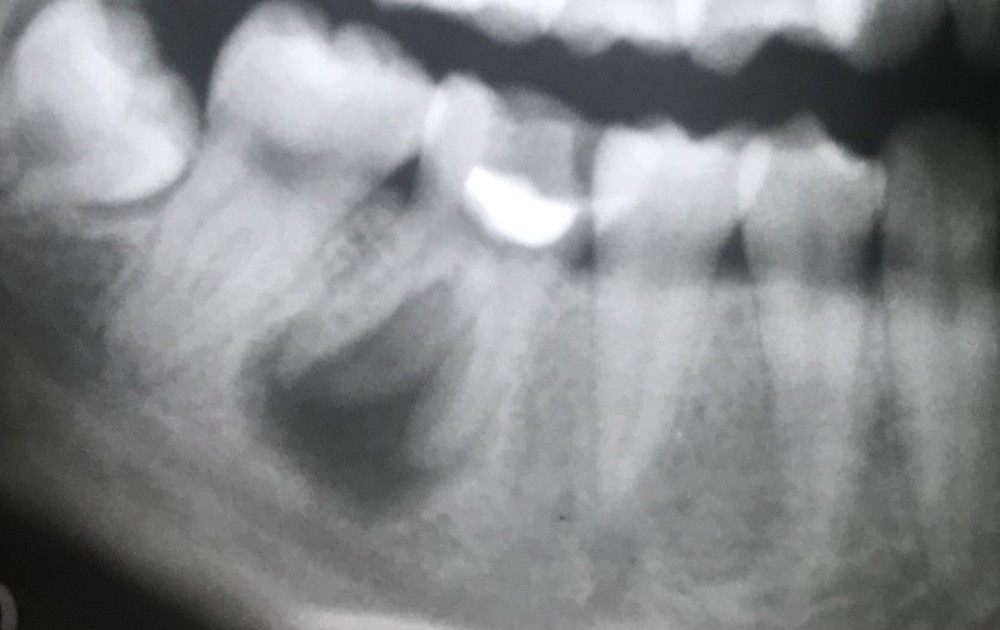

初診時 20歳6ヶ月、主訴は右下の顎の痛み

下の画像は初診時のものです。

骨吸収がかなり広範囲です。

下顎管への影響も心配されます。